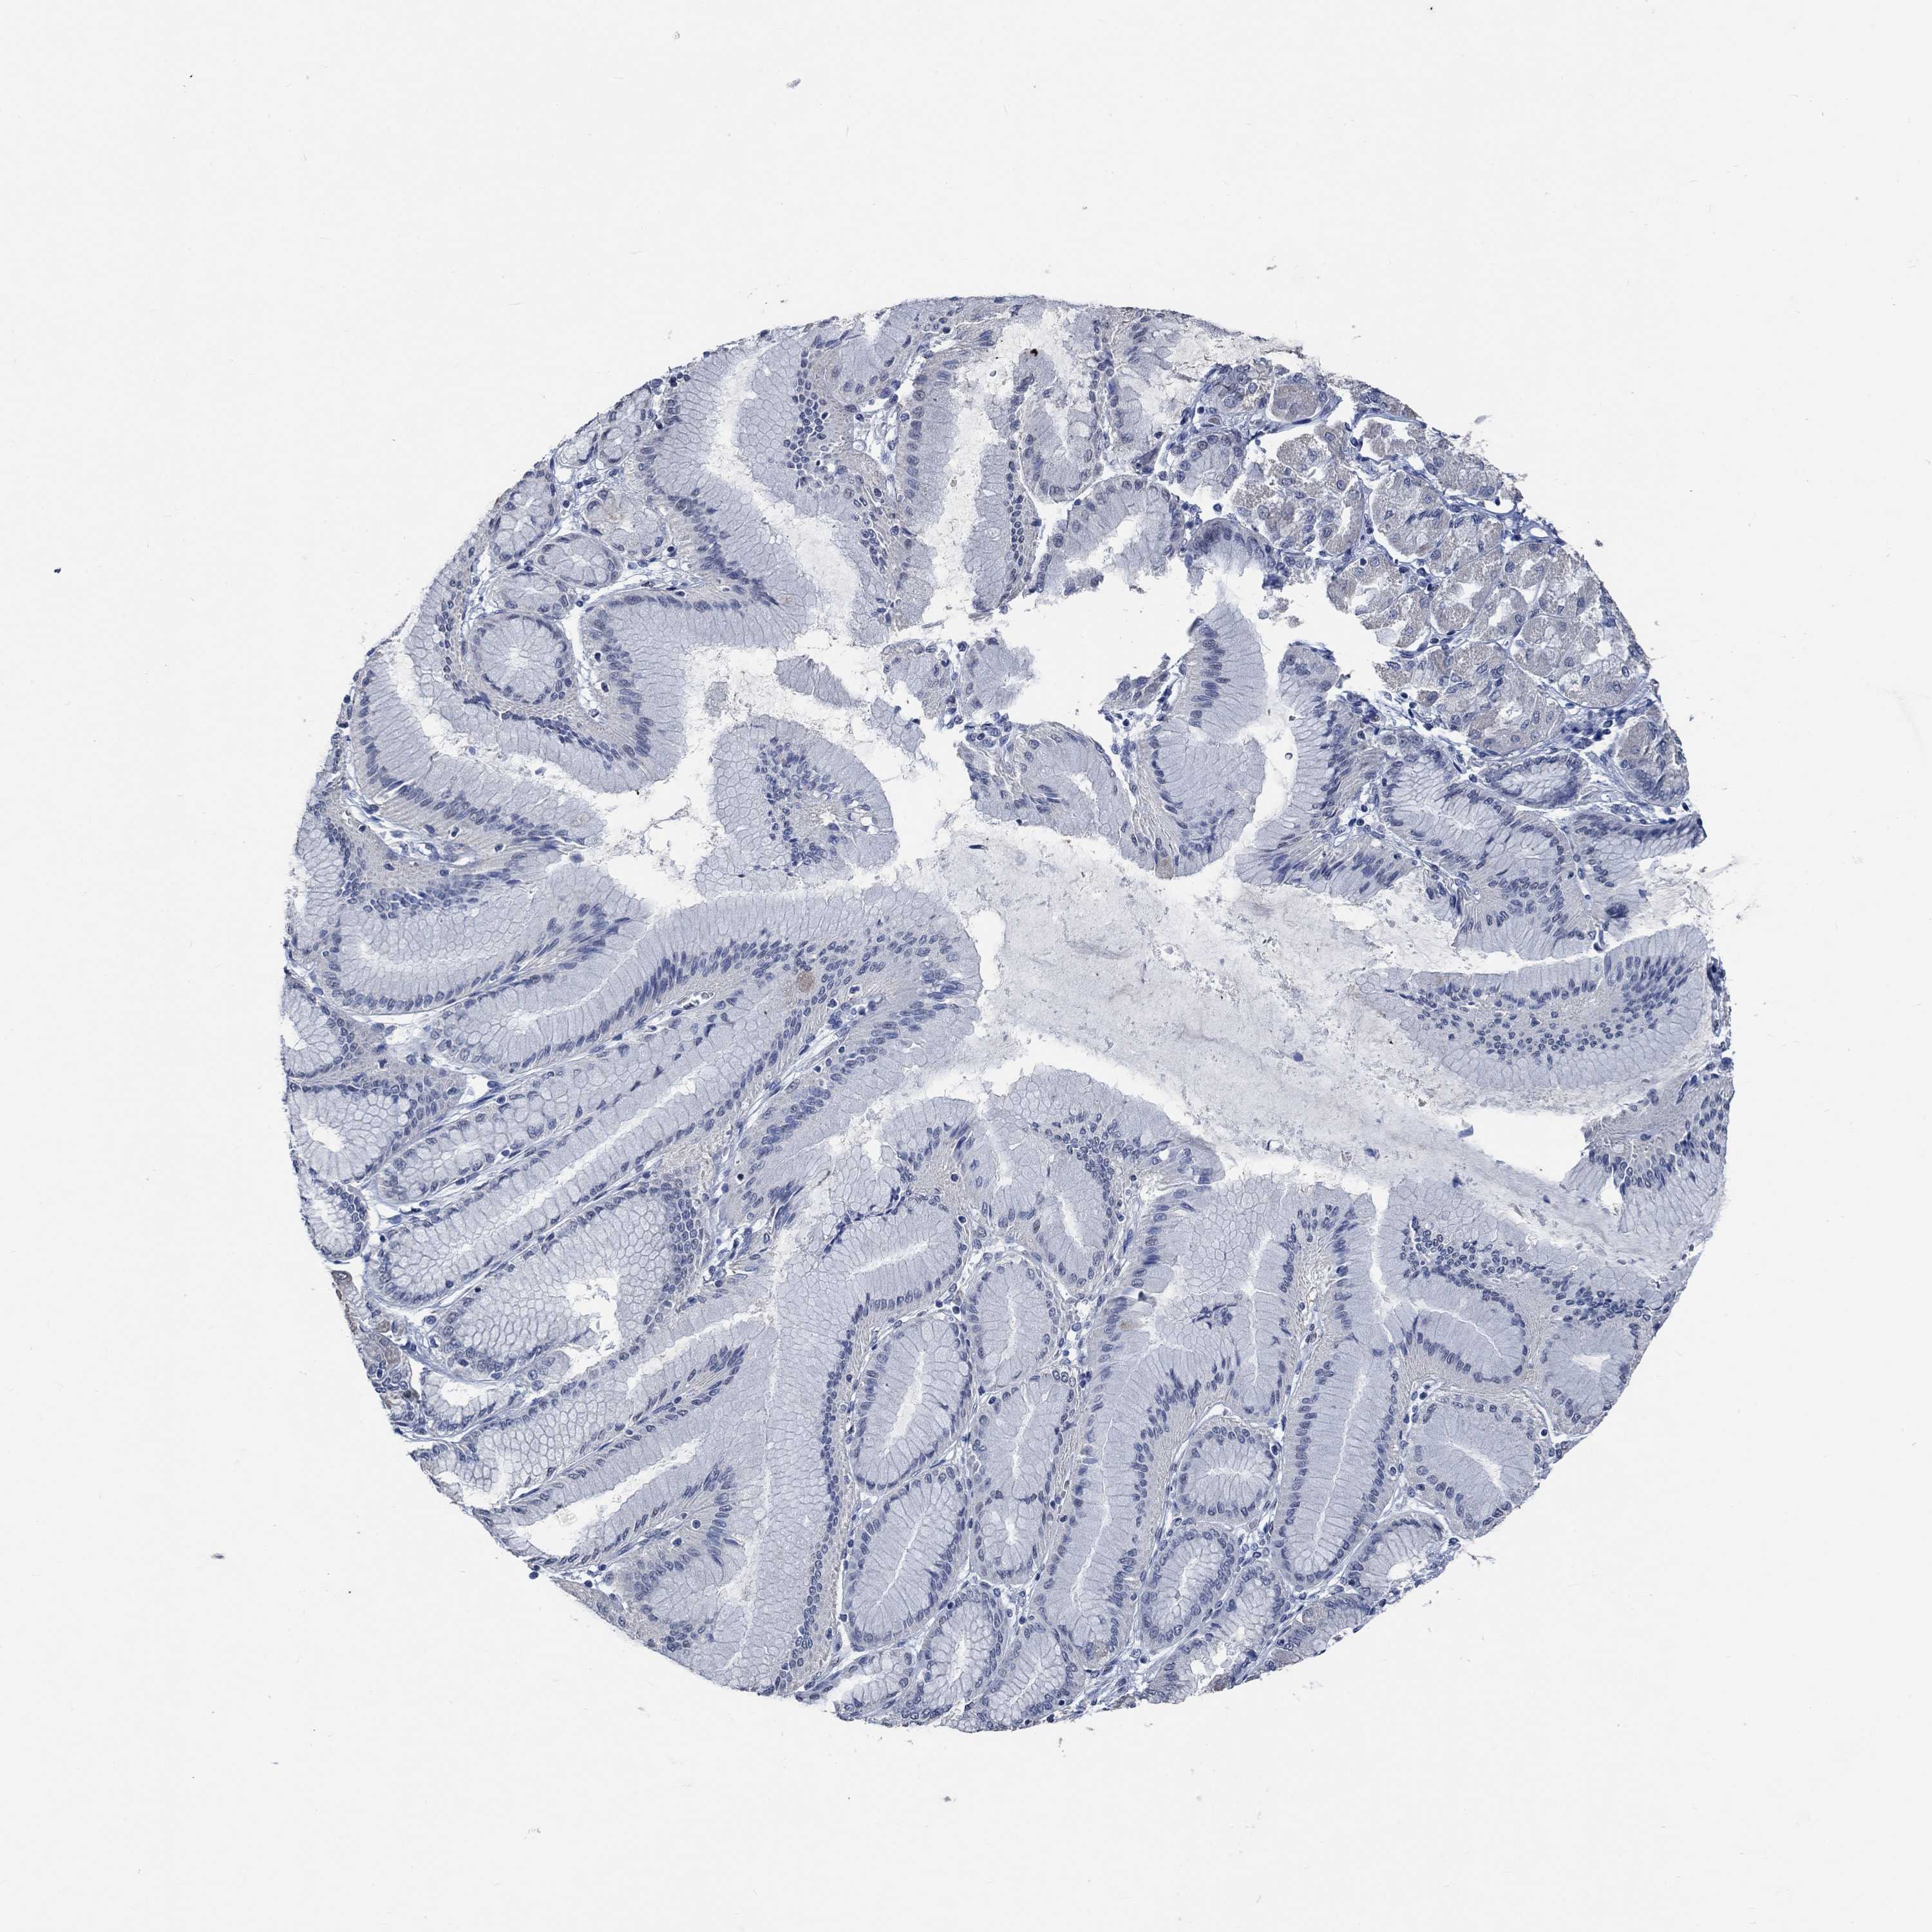

STOMACH CANCER - Protein expressioni

A mouse-over function shows sample information and annotation data. Click on an image to view it in a full screen mode. Samples can be filtered based on level of antibody staining by selecting one or several of the following categories: high, medium, low and not detected. The assay and annotation is described here.

Note that samples used for immunohistochemistry by the Human Protein Atlas do not correspond to samples in the TCGA dataset.

Antibody stainingi

Antibody staining in the annotated cell types in the current human tissue is reported as not detected, low, medium, or high, based on conventional immunohistochemistry profiling in selected tissues. This score is based on the combination of the staining intensity and fraction of stained cells.

Each image is clickable and will lead to virtual microscopy that enables deeper exploration of all samples and also displays staining intensity scores, fraction scores and subcellular localization as well as patient and tissue information for each sample.

Antibody HPA021186

Antibody HPA065801

Staining

High

Medium

Low

Not detected

Intensity

Strong

Moderate

Weak

Negative

Quantity

>75%

75%-25%

<25%

None

Location

Nuclear

Cytoplasmic/membranous

Cytoplasmic/membranous,nuclear

Adenocarcinoma, NOS

Adenocarcinoma, High grade